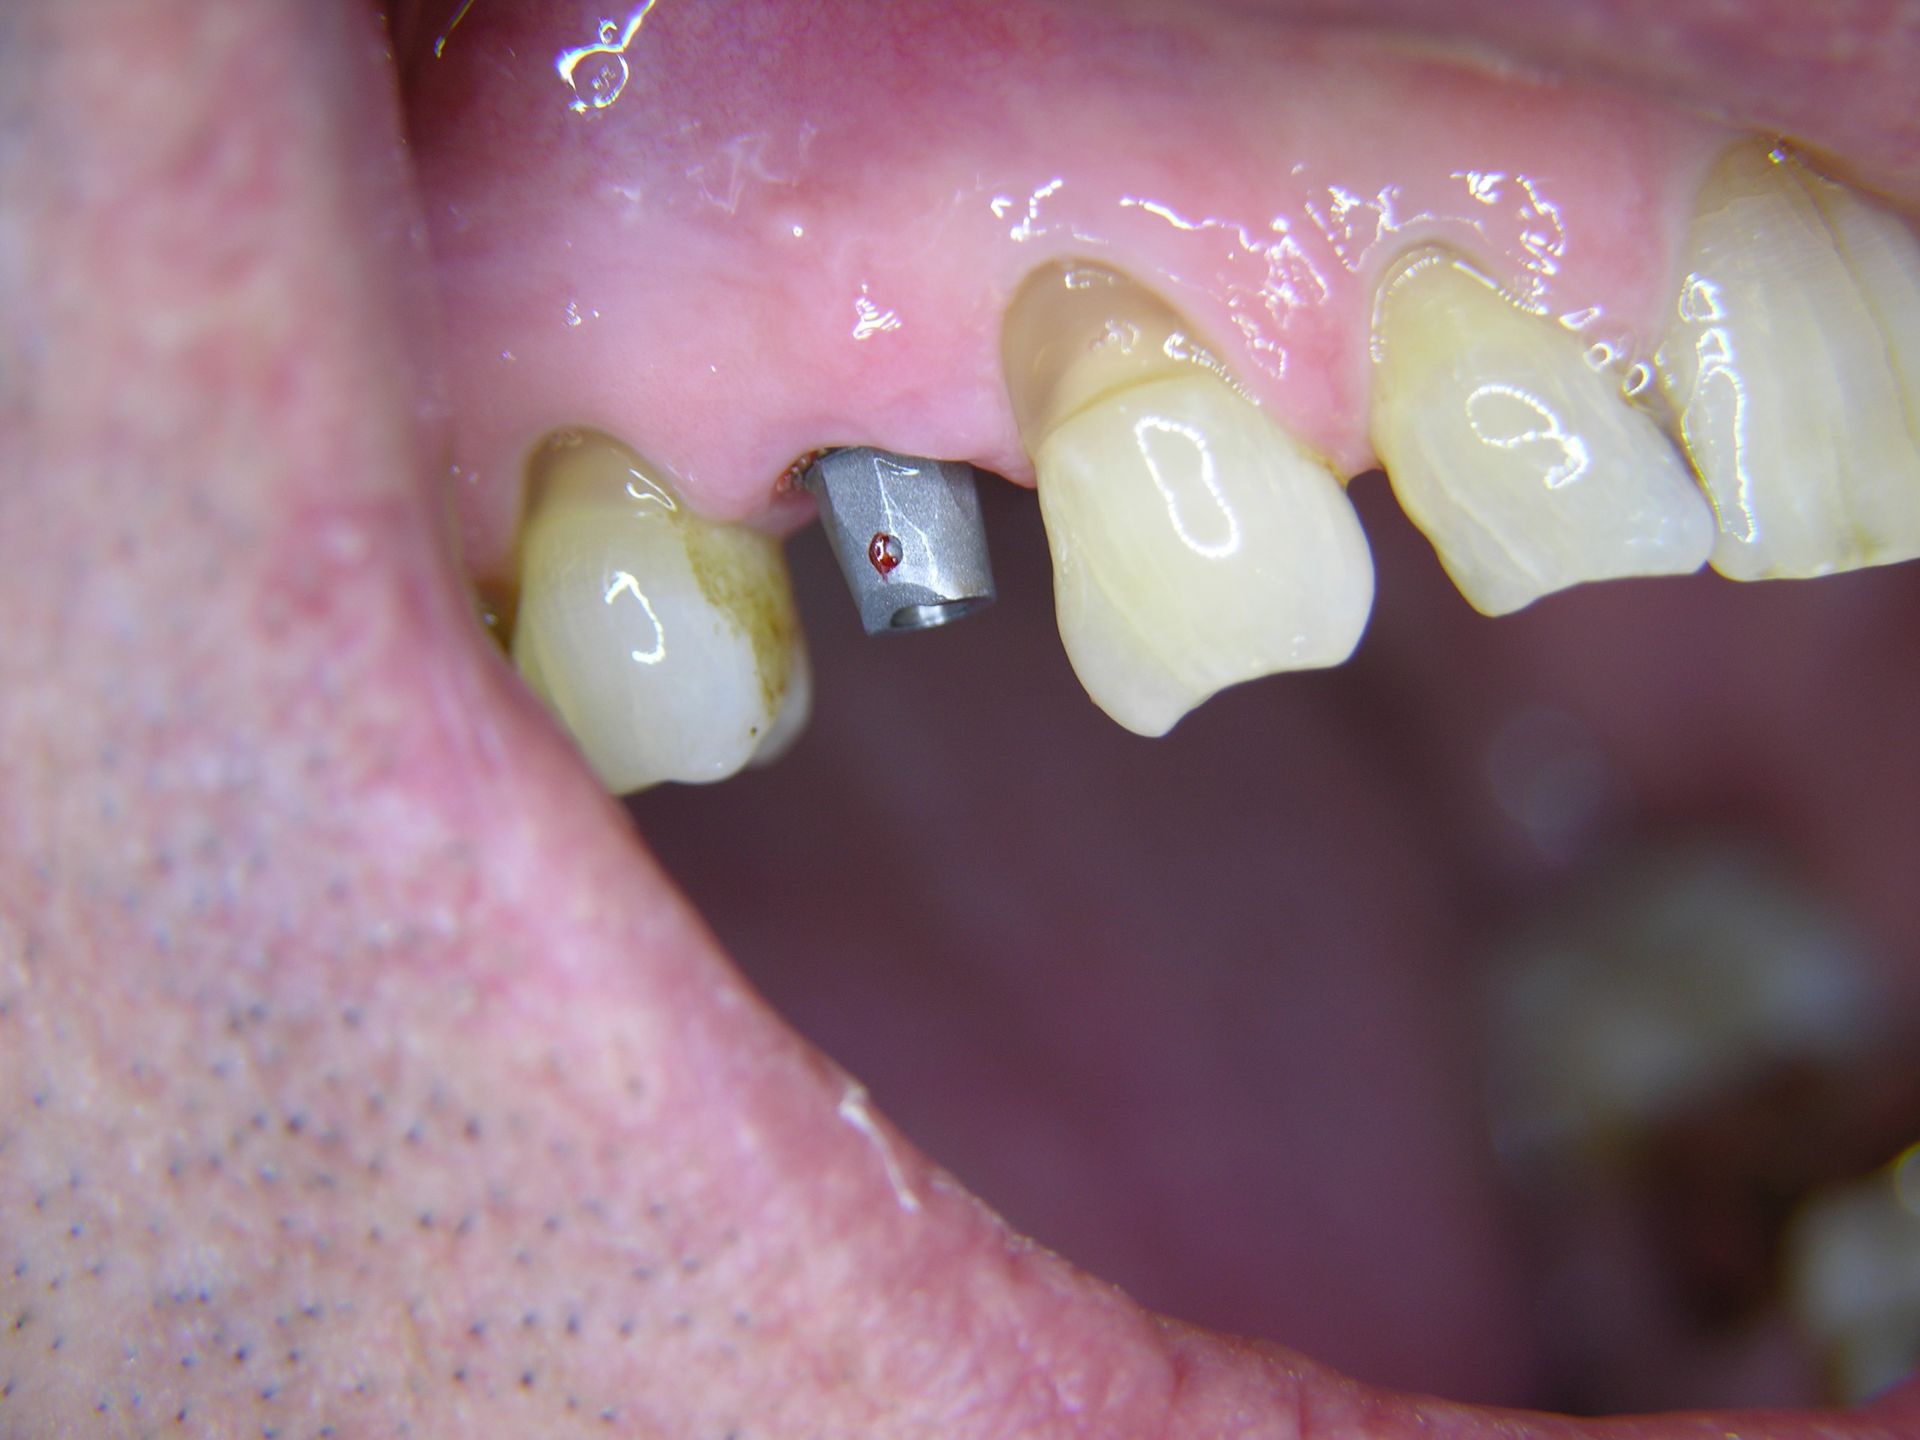

Beispiele von Versorgungen